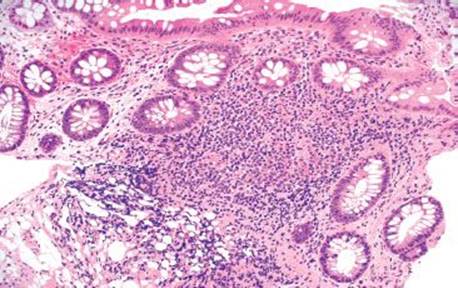

Figure 4.259 PCI. Histologic sections show multiple cyst-like spaces in the muscularis propria.

Figure 4.260 PCI. Alternate image, same patient.

Figure 4.261 PCI. Higher power shows that the cyst-like spaces are lined by histiocytes and foreign body giant cells.

Figure 4.262 PCI. Highest power shows the bland features of the foreign body giant cells lining the empty spaces.